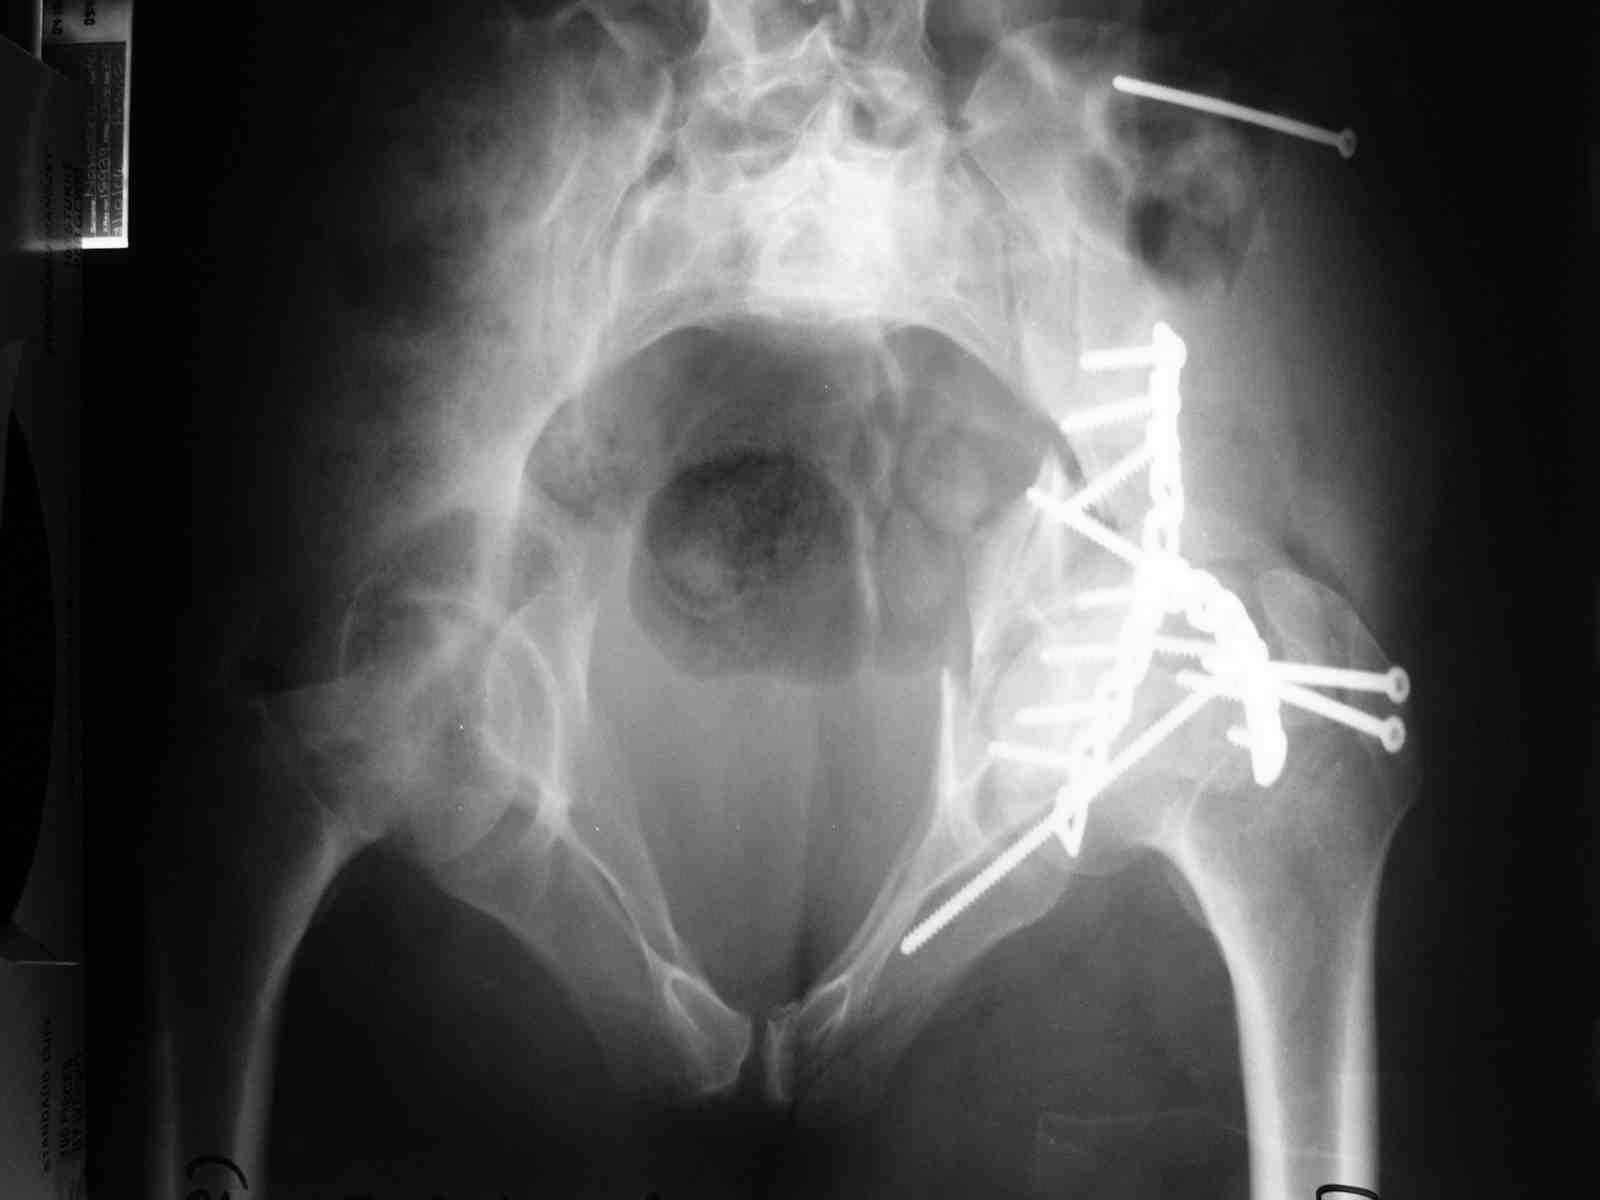

Спасибо за комментарии и рекомендации. Откровенно говоря, больного я прооперировал на прошлой неделе, через 5 дней после аварии и проблем с ним пока никаких нет, на удивление при достаточно обширной диссекции (илиофеморальный доступ) болей практически нет, так что больной самостоятельно садится в кровати, выполняет активные движения в оперированном суставе, сгибая до 60 градусов пока, далее с ассистенцией.

Причиной обращения к сообществу были возникшие непосредственно после операции сомнения и разочарования полученным качеством репозиции: а надо ли было трогать перелом вообще, репозиция передней колонны технически была очень сложна для меня, хотя реконструкции была в той же последовательности, что Д-р А.В.Рунков рекомендовал, в какой-то момент безуспешных манипуляций стал думать о *вторичной конгруэнтности*, которую не так давно обсуждали на

форуме и скелетном вытяжении. С репозицией и фиксацией задней колонны и отдельно задне-верхней стенки впадины проблем не возникло. Послеоп. Рг граммы в приложении. Если возникнут какие-либо дополнения или поправки - был бы признателен.